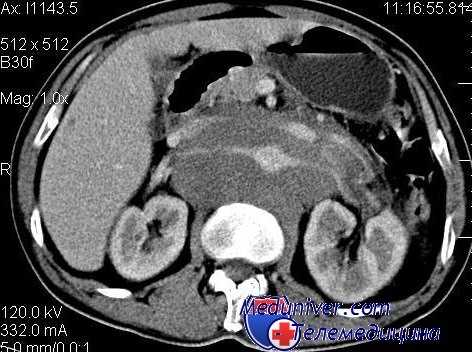

КТ органов брюшной полости при лимфоме

Печень оценивается по следующим критериям: размеры органа, средняя плотность (КА), степень однородности показателей плотности, состояние поверхности органа (ровная или неровная). Размеры печени измеряются по краниокаудальному размеру и поперечному размеру от наружного края правой доли до медиального края хвостатой доли печени («печеночно-абдоминальный индекс», норма до 50%).

Средняя плотность печени и ее структура (однородная или неоднородная) определяются путем сравнения среднеарифметических значений КА в 3-5 свободно выбираемых бессосудистых участках паренхимы. Плотность печени считается пониженной при плотности ниже 57 HU, а структура органа неоднородной — при разнице значений среднеарифметической плотности паренхимы более 6-8 HU.

Селезенку оценивают по ее размерам, средним показателям плотности и структуре. Размеры органа оценивают по переднезаднему размеру между передним и задним краем селезенки и поперечному — от наружного края перпендикулярно продольной оси до наиболее отдаленного края внутренней поверхности, в том числе до задней выступающей части медиального края. В норме поперечный размер селезенки на томограммах составляет до 100 мм на 50 мм. Показатели плотности селезенки измеряют так же, как и печени. Оценивают также среднюю плотность и однородность структуры.

Структуру селезенки считают неоднородной, если при замерах плотности в трех областях разница показателей КА одной их них 3-5 HU. В норме средняя плотность селезенки около 52,1 ± 0,8 HU.

При диффузном поражении печени и селезенки у больных лимфомами определяются следующие КТ-критерии: гепатоспленомегалия, неоднородная плотность и снижение средней плотности паренхимы. У 10% больных диффузное поражение отмечается без увеличения органов, но при этом снижается их плотность и имеется неоднородная структура.

Узловые поражения печени и селезенки встречаются крайне редко (1-4%). При этом размеры лимфоидных очагов колеблются от 15 мм до 35 мм. В селезенке у части больных встречаются множественные образования. Плотность образований составляет 35-42 HU. Контуры их нечеткие, но без перифокальных изменений в ткани органа.